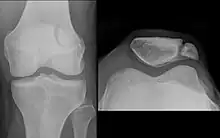

Transverse fracture of patella